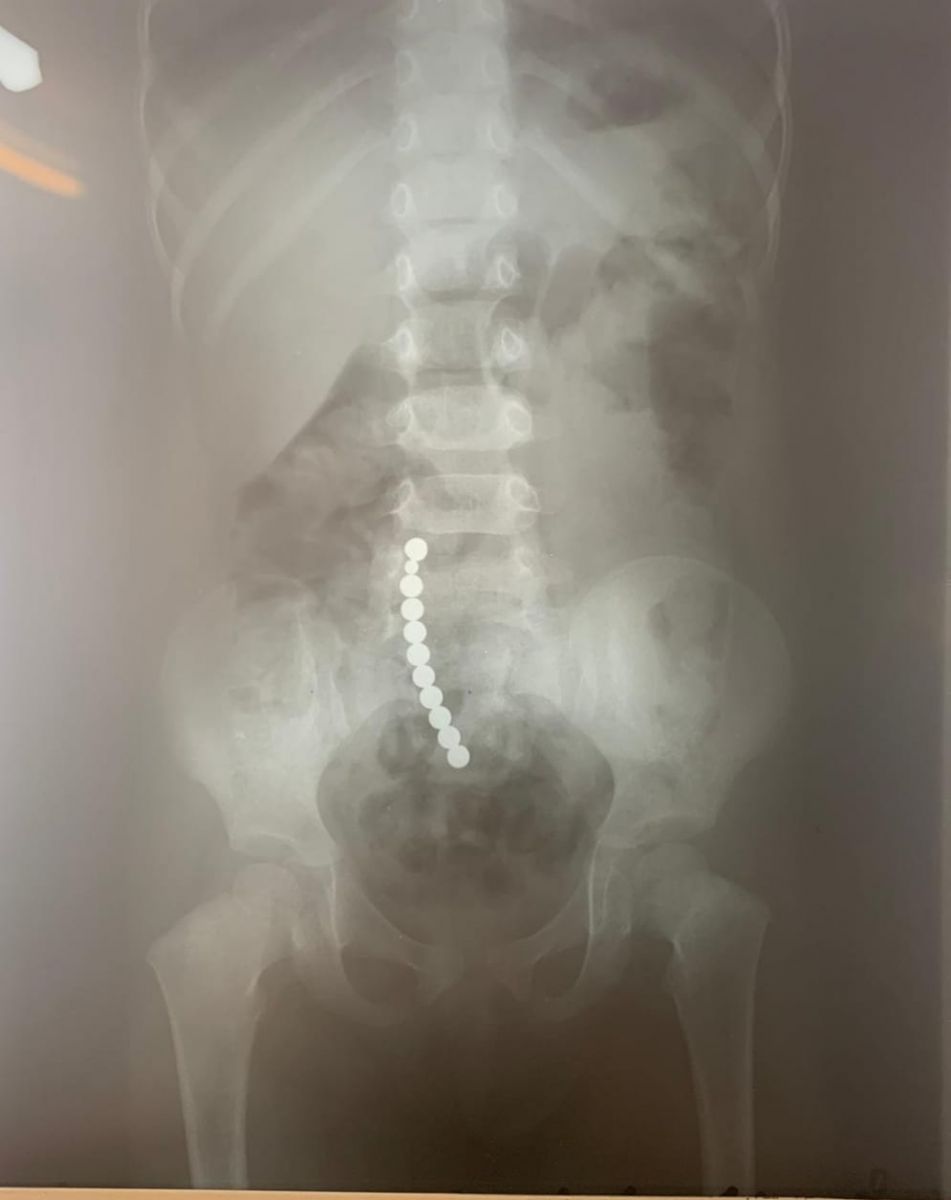

„Acești magneți sunt foarte puternici, iar ingestia lor poate duce la probleme gastrointestinale grave. Odată înghițiți sunt atrași unul spre altul chiar dacă se găsesc în secțiuni diferite ale tubului digestiv. O ansă intestinală prinsă între acești magneți se poate perfora ducând la tratament chirurgical de urgență. În secția noastră, de la începutul anului s-au prezentat trei cazuri, două fete și un băiat, cu vârste cuprinse între 2 și 4 ani. Aceștia au suferit perforații la nivelul intestinului subțire și au necesitat intervenții pentru îndepărtarea porțiunii de intestin afectate”,

dr. Adriana Constantineanu.